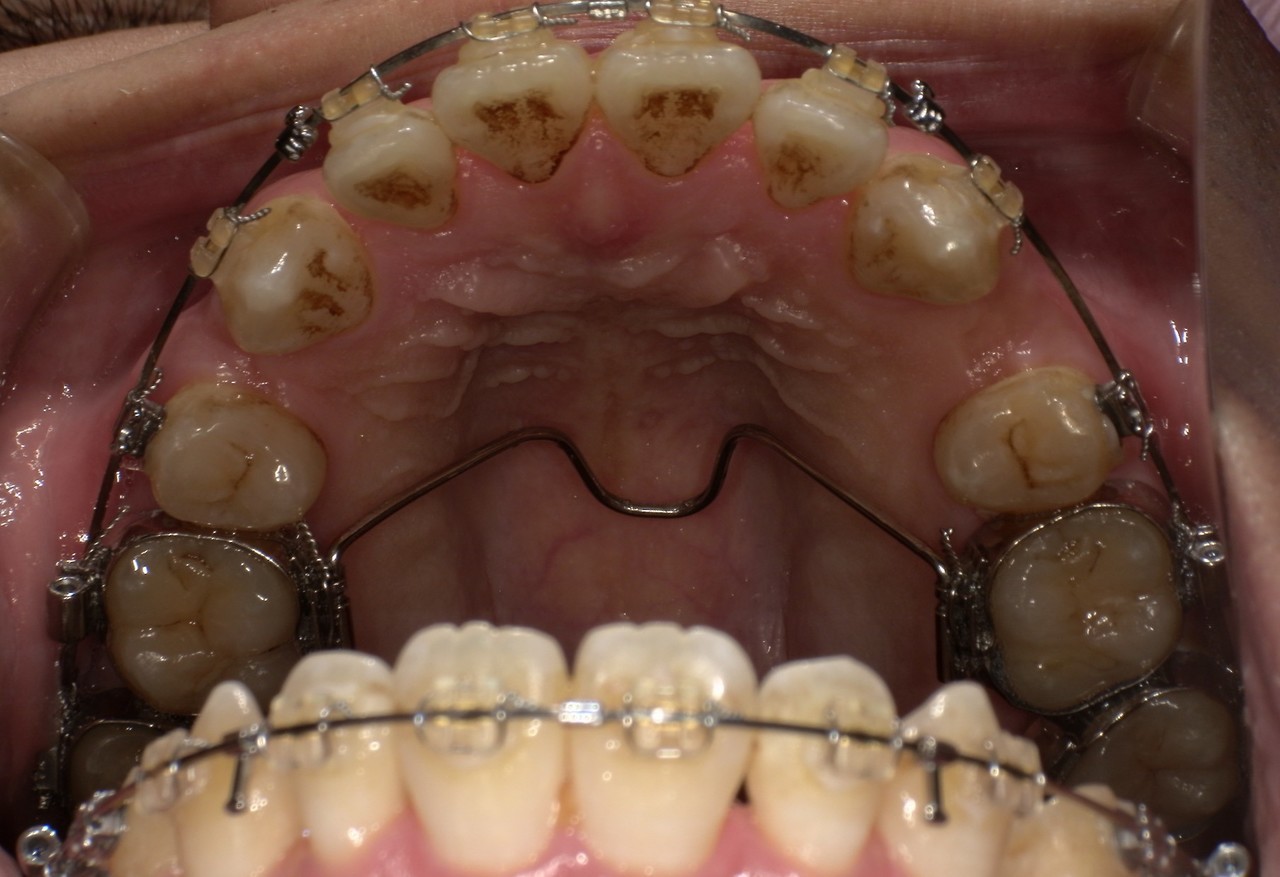

ステイン除去

BEFORE

AFTER

年齢:70代男性

治療内容:エアーフローによる歯の着色汚れ、ステイン除去

治療期間/通院回数:1回

費用: ステインコース 8,800円

リスク・副作用

①効果には個人差があり、着色汚れによっては一度に取りきれない場合があります。

施術後数時間以内に、着色効果の強いもの(コーヒー・紅茶・喫煙など)を摂取すると、歯に色素沈着が起こる可能性があります。

パウダーの刺激により歯ぐきから出血する可能性があります(痛みはほとんどありません)。